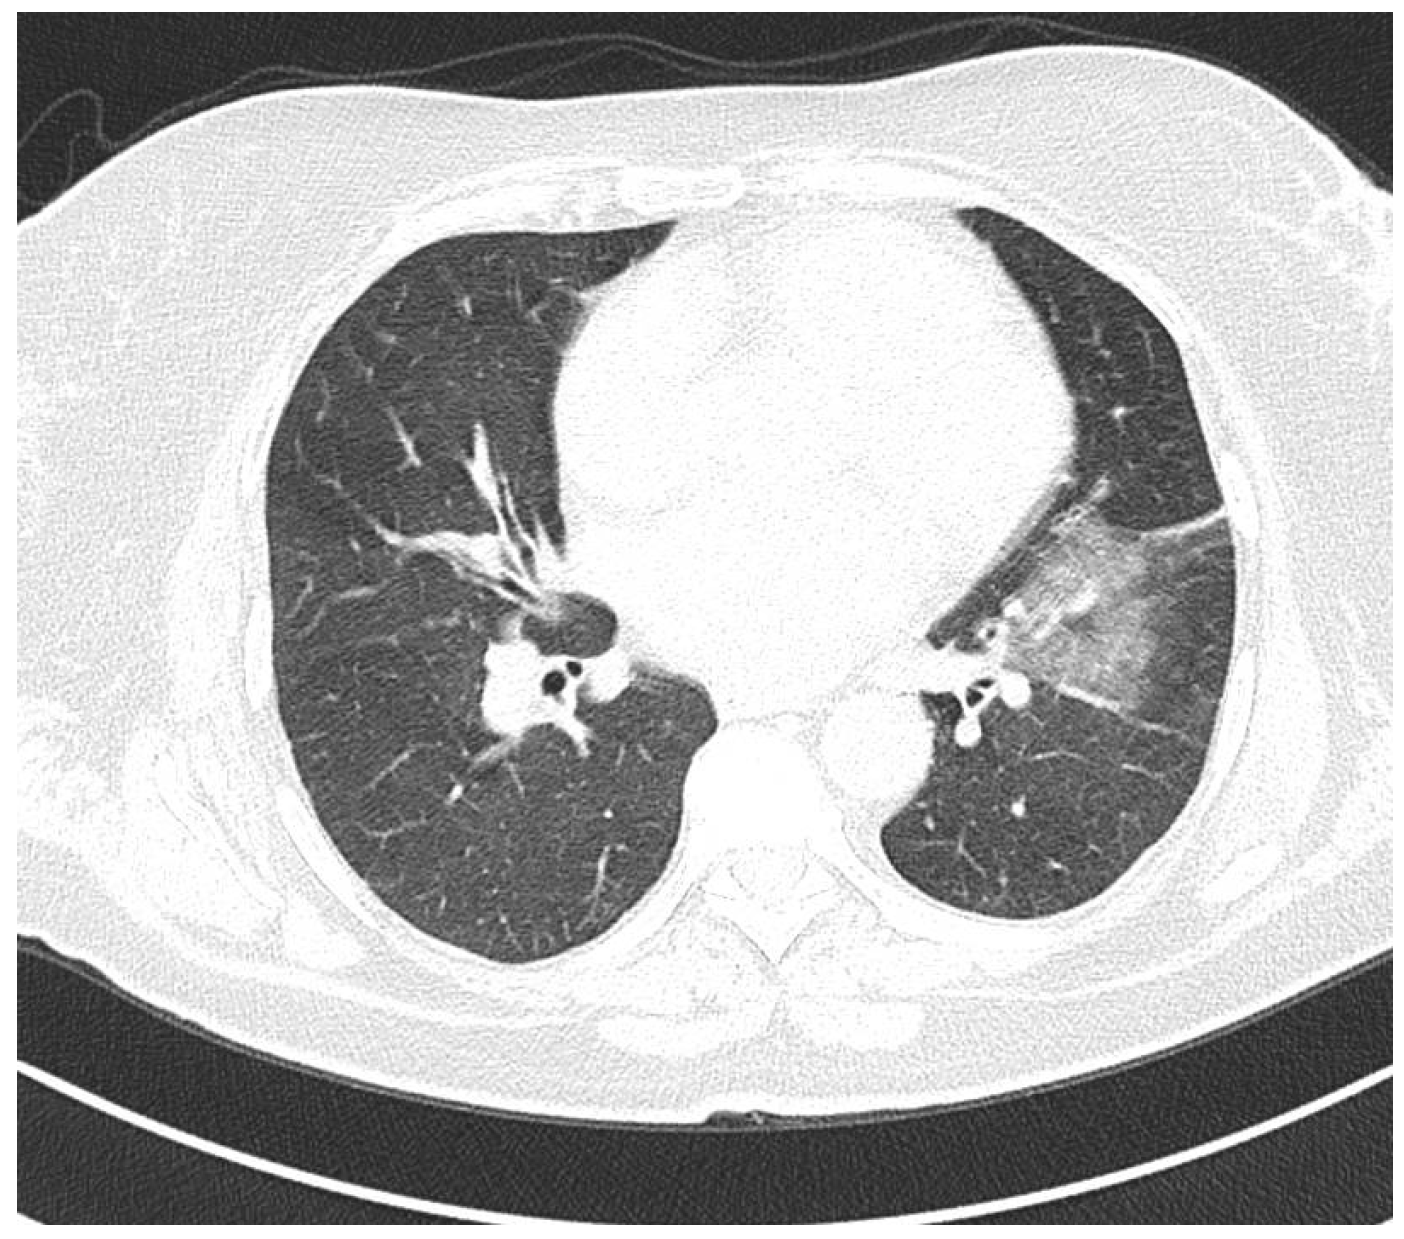

Rare Case of Grade 3 Undifferentiated Pleomorphic Sarcoma in Left Atrium, Mitral Valve, and Papillary Muscle

2. Case Report